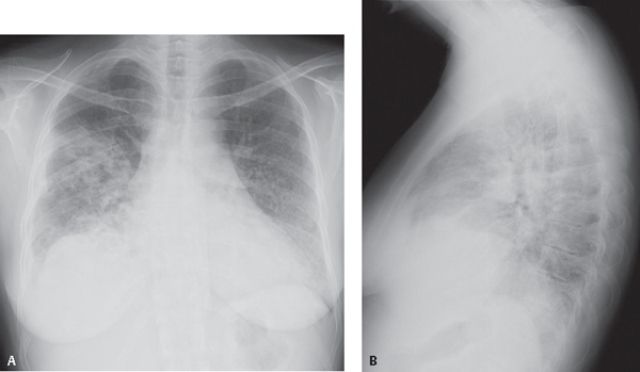

Diagnosis didasarkan dari gejala-gejala yang ada dan hasil pemeriksaan fisik. Untuk membantu memastikan diagnosis bisa dilakukan pemeriksaan lain seperti :

1. foto rontgen dada